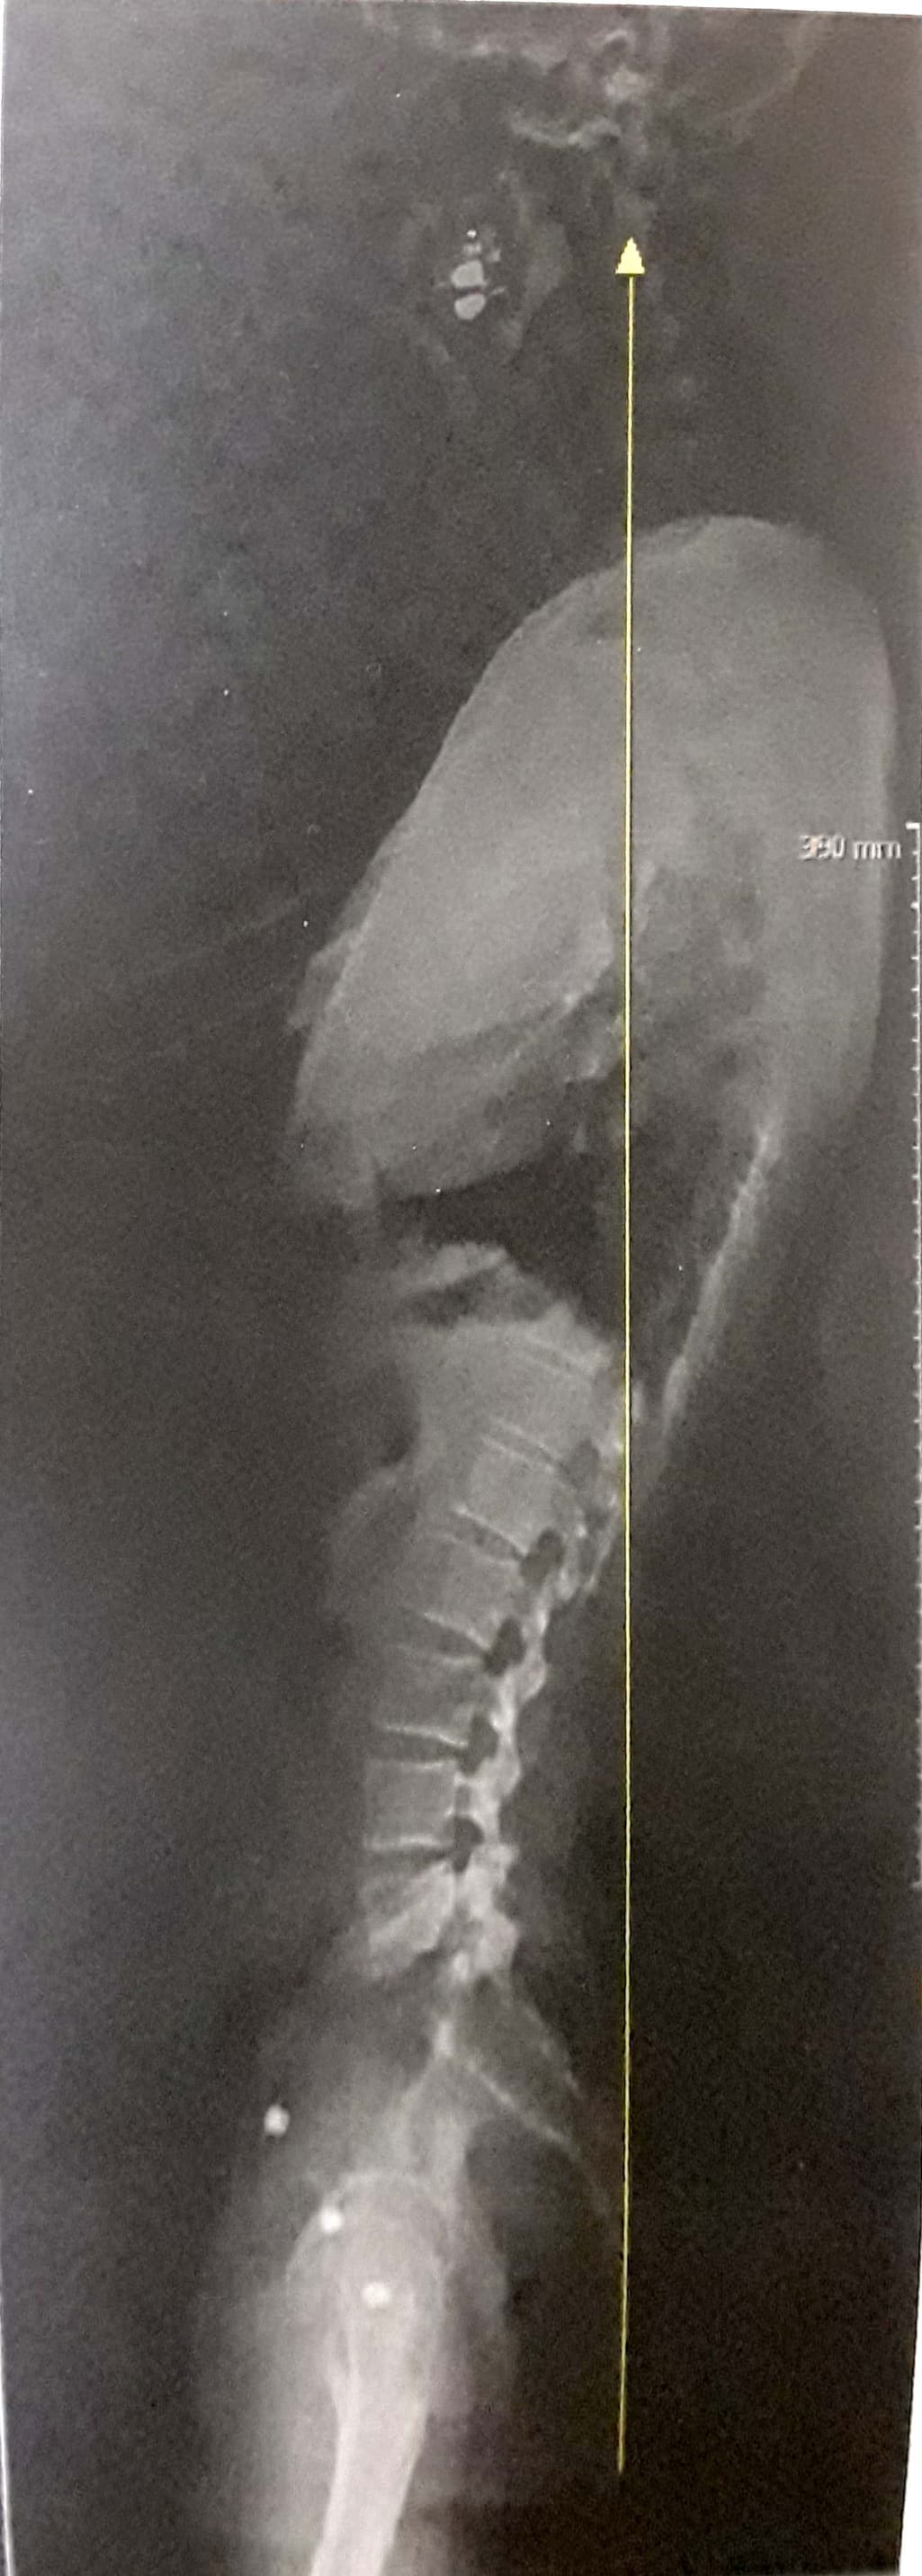

일자목 일자등 확인 부탁드립니다.

일자목 일자등 인 것 같은데 맞나요?

거북목과 일자목 재활 운동 방법이 다르다고 해서 확인 부탁드립니다.

눈도 침침하고 두통이 생기고 해서 원인을 몰랐는데 자세가 문제 인 것같아서

재활운동을 집에서 해보려고 합니다. 도움이 될까요?

사진상 상태가 많이 안좋다면 정형외과에서 도수치료 받는게 좋을까요?